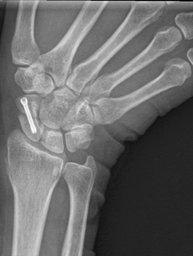

近日,骨科中心主任吴超带领手术团队完成川南首例机器人辅助舟骨经皮螺钉精准置入内固定术;螺钉精准置入骨折线处,仅仅留下0.5毫米的伤口,患者就可恢复正常的手部结构和功能。术后复查X片及CT均显示螺钉位置良好,起到很好的固定作用;患者已在节前康复出院,过上一个幸福快乐的春节。

术前X片显示骨折处        术后X片显示螺钉位置良好

舟骨骨折与股骨颈骨折、小腿中下三分之一部位的骨折,通称为人体三大比较难愈合的骨折部位。对于骨折端异位的患者,必须通过对齐骨折线创造骨折愈合条件,否则容易导致舟骨骨折断端不愈合,甚至出现舟骨坏死的情况。机器人辅助的经皮舟骨螺钉内固定能在极小的创伤下,帮助舟骨骨折端精准地对齐和固定,避免保守治疗不愈合的风险和常规手术创伤的危害,达到较好的治疗效果。